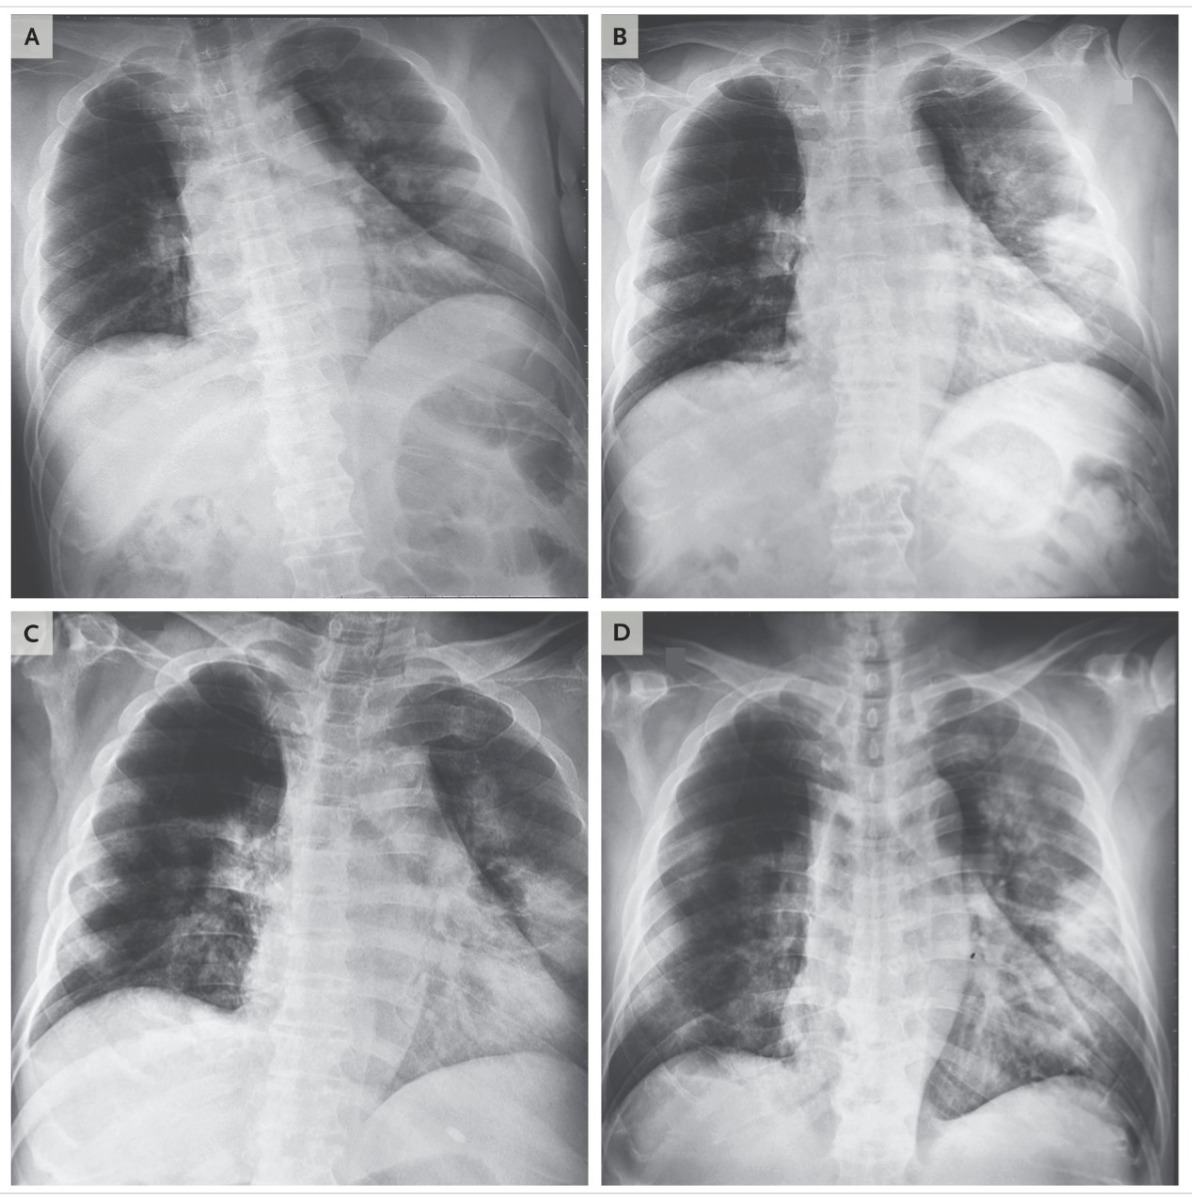

- Khoảng 1/4 bệnh nhân virus có triệu chứng hô hấp nặng, có thể dẫn đến nhiễm trùng phổi do virus Corona hay do virus kết hợp với vi trùng và các bệnh lý khác. Trong trường hợp nặng, bệnh nhân cần thêm ống thở oxy, có thể cần máy thở (được đặt ống thở nội soi). Do hệ hô hấp suy giảm, bệnh nhân sẽ có thêm rủi ro các bệnh về phổi, tim mạch, gan, hay thần kinh, dẫn đến tỉ lệ bệnh năng hay tử vong cao.